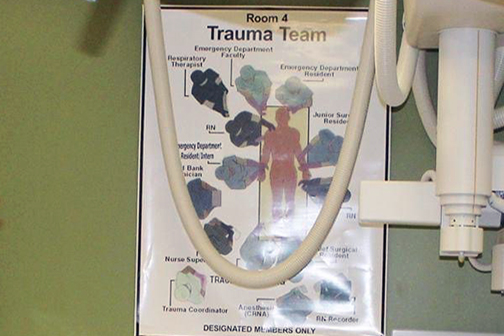

LSU Health New Orleans Study Reveals Economic Burden of Gun Violence

A study led by Christopher Marrero, MD, Associate Professor of Clinical Orthopaedic Surgery at LSU Health New Orleans School of Medicine, reports that the net loss for treating acute firearm injuries at one Level I Trauma Center was $20.3 million over a four-year period. The results are published online in the American Journal of Preventive Medicine. More